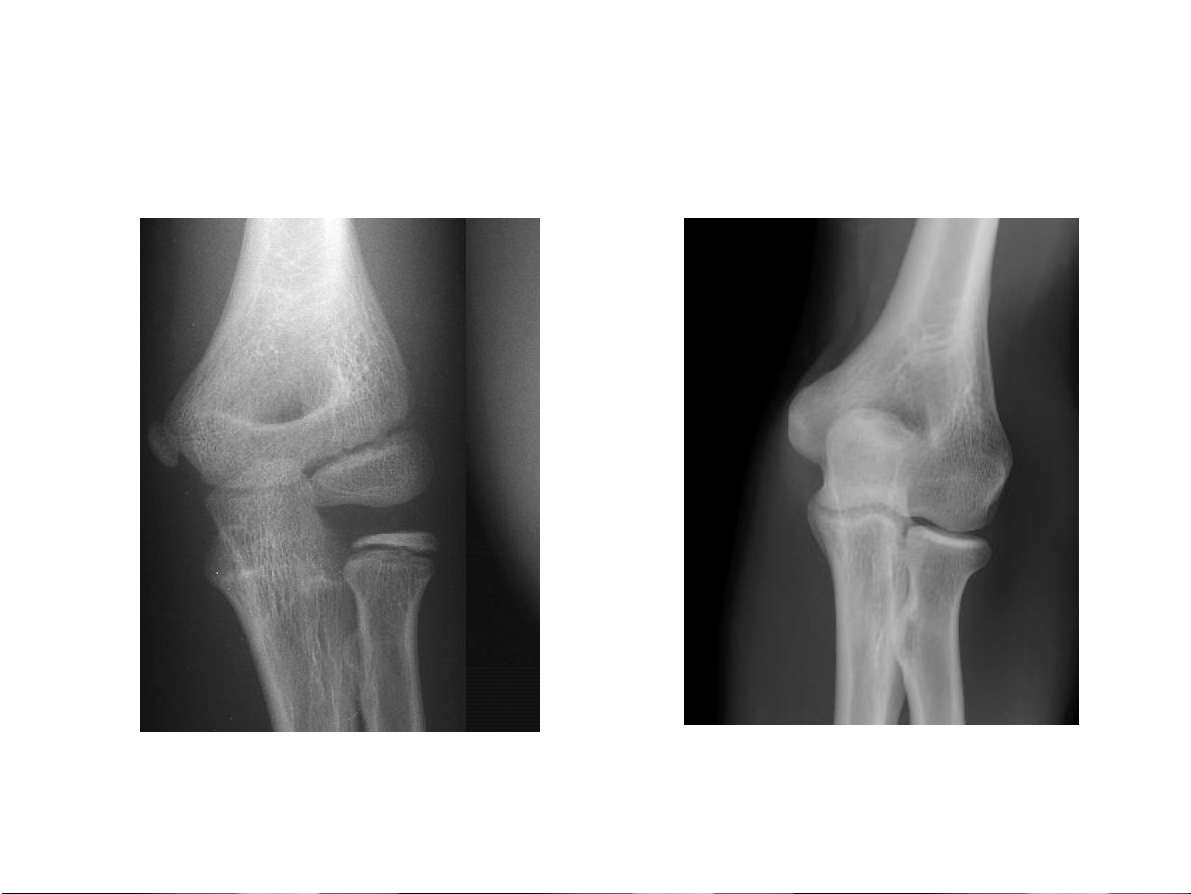

Bất thường về cấu trúc Huỷ xương 1.Giới hạn tổn thương

• Không rõ, vùng chuyển tiếp

rộng tổn thương tiến triển nhanh

• Rõ, vùng chuyển tiếp hẹp lành tính 31-Jan-23 CĐHA Cơ-Xương-Khớp

• Không rõ, vùng chuyển

tiếp rộng tổn thương tiến triển nhanh

• Rõ, vùng chuyển tiếp hẹp lành tính. 31-Jan-23 CĐHA Cơ-Xương-Khớp Huỷ xương 31-Jan-23 CĐHA Cơ-Xương-Khớp Huỷ xương 31-Jan-23 CĐHA Cơ-Xương-Khớp 31-Jan-23 CĐHA Cơ-Xương-Khớp